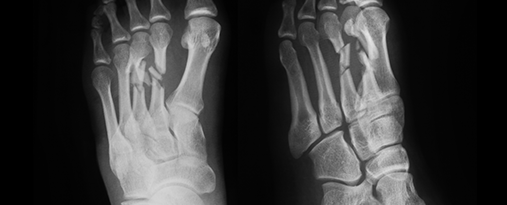

엑스선을 이용하여 병변 부위의 상태를 확인합니다.

통증 부위를 압박하는 자세로 검사합니다.